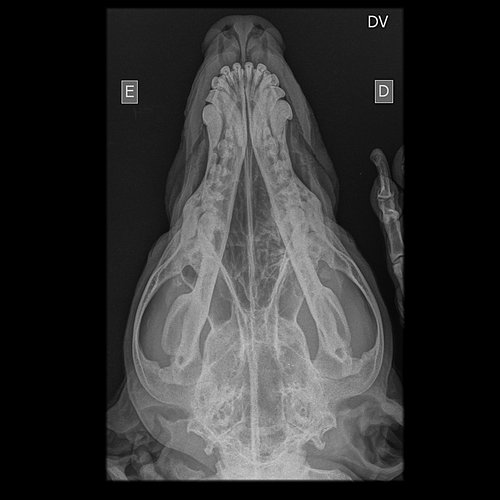

Radiografias em projeções: LATEROLATERAL ESQUERDA E DORSOVENTRAL

- Nota-se discreta proliferação óssea no aspecto ventral e medial da porção média/caudal do ramo

horizontal da mandíbula direita;

- Discreta opacificação da cavidade nasal direita;

- Cavidade nasal esquerda preservada;

- Septo nasal mantido;

- Osso nasal e frontal preservados;

- Preservação das articulações temporomandibulares;

- Em incidência dorsoventral, imagem que sugere opacificação das bulas timpânicas;

- Condutos auditivos externos sem sinais de alterações;

- Nada mais digno de nota na região em estudo, pelas incidências realizadas.